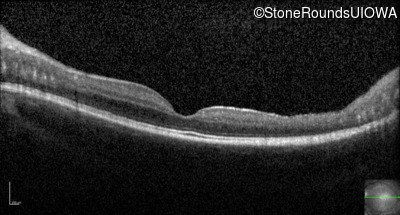

Optical Coherence Tomography - Left - 20/40 +2 sc

Exemplar / OCT Stack

OCT Stack